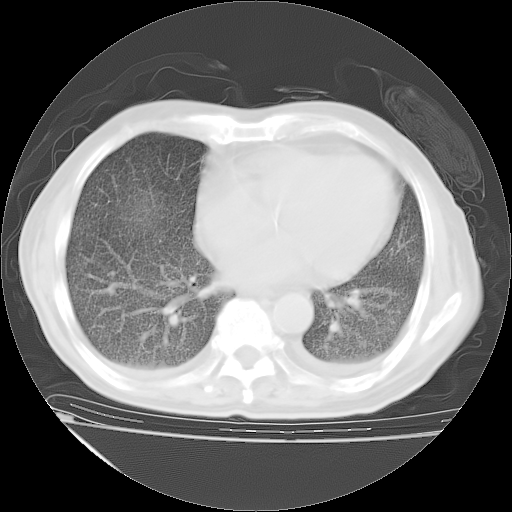

经过24天治疗,岳父的病情基本稳定。生活基本可以自理,可以下床活动。呼吸困难早已消失。体温基本正常。

只是甲强龙用80mg时血小板升到正常,改为60mg后又降到63×10*9/L。

主要治疗甲强龙80mg×14天,60mg×10天;同时抗结核(异烟肼+利福平+乙胺丁醇)。环磷酰胺0.1 tid 10天。

特别感谢胡教授、高管、桃子版主给出关键的治疗建议。桃版把所有肺部影像和全部临床资料请所在医院呼吸科、感染病科、结核科、临床免疫科专家会诊。临床免疫科专家制定了完整的治疗方案。